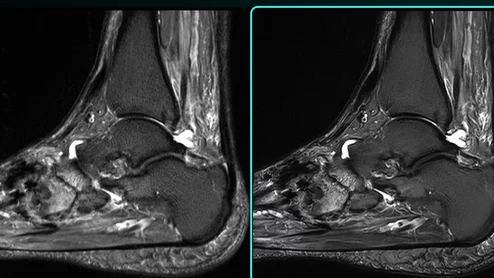

Prenuvo MRI

Sean Clifford filed the lawsuit Sept. 24, 2024, in the New York State Supreme Court, contending a radiologist failed to spot signs of a forthcoming stroke.